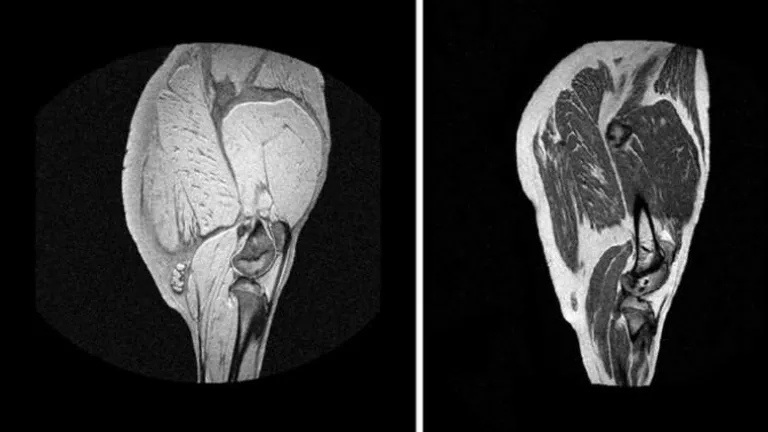

Uno de los miembros que realiza esta investigación es Pablo García, que ha pasado por los micrófonos de 'La Tarde' para explicarnos por qué lo hacen y como es el proceso: "A uno le da rabia cuando se desplaza a un sitio, se compra un jamón y cuando lo va a abrir no está todo lo bueno que debería". El proceso es el mismo que utilizan en los hospitales con pacientes: "Es como si cortaras el jamón, la imagen es muy buena, es como magia, con características de esas imágenes, conseguimos predecir averiguar como esta el jamón al cabo de dos años. Se ve perfectamente que tipo de alimentación, lo que ha comido, como esta de veteado, si es un tipo de jamón u otro".